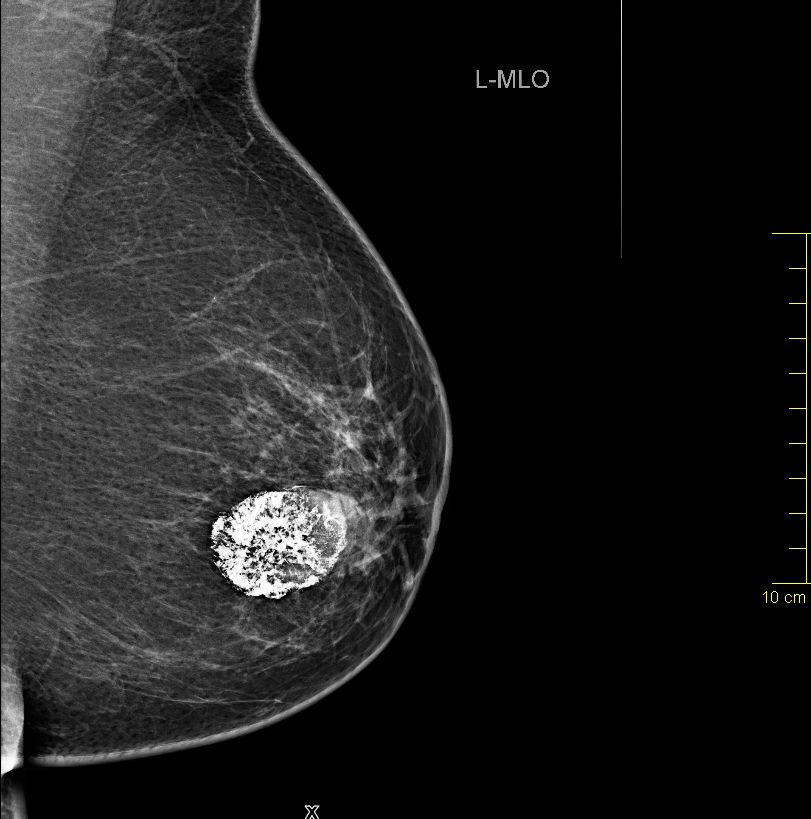

| Fall | 72-jährige Frau, bei der vor 5 Jahren ein gutartiger Tumor diagnostiziert wurde. Vor 8 Monaten war der Tumor auf 4cm angewachsen. Die Exzision wurde empfohlen. Jetzt war der Tumor 66 mm groß, sehr hart und teilweise verkalkt. | |||

| vor 8 Monaten | Mammographie links MLO.![]() |

Vergrößerung.![]() | ||